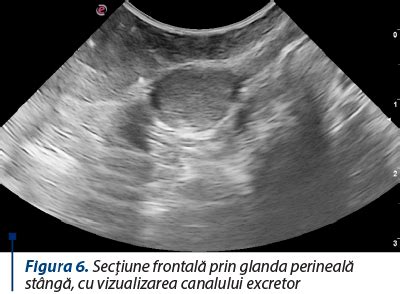

- Ecografie endoanală și RMN pentru identificarea traiectului fistulos: Aceste investigații pot oferi o imagine completă a traiectului fistulos și a relației acestuia cu sfincterul anal.